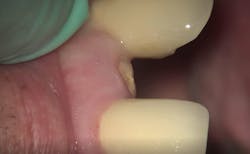

- Chief complaint: Fracture of clinical crown tooth no. 10

- Clinical findings: Oblique fracture no. 10 to bone level

- Diagnosis: Unrestorable maxillary lateral incisor

- Treatment plan: Extraction/immediate implant placement with nonfunctional provisional